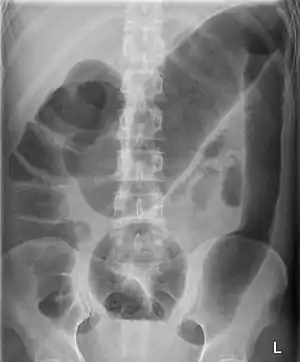

Toxic megacolon associated with ulcerative colitis.

Abdominal X-ray showing megacolon.

Diagnosis is achieved mainly by plain and contrasted radiographical and ultrasound imaging. Colonic marker transit studies are useful to distinguish colonic inertia from functional outlet obstruction causes. In this test, the patient swallows a water-soluble bolus of radiocontrast agent and films are obtained 1, 3, and 5 days later. Patients with colonic inertia show the marker spread throughout the large intestines, while patients with outlet obstruction exhibit slow accumulations of markers in some places. A colonoscopy can also be used to rule out mechanical obstructive causes. Anorectal manometry may help to differentiate acquired from congenital forms. Rectal biopsy is recommended to make a final diagnosis of Hirschsprung disease.[12]